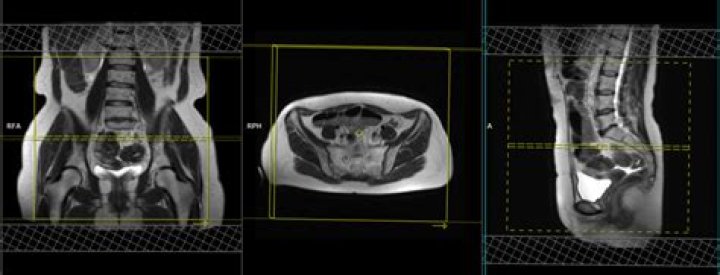

Can you see endometriosis on pelvic MRI?

Pelvic magnetic resonance imaging (MRI) is one imaging technique that doctors may use to help diagnose endometriosis. The test provides a picture of organs inside the pelvic cavity and shows endometrial growths that may require further investigation.

MRI is particularly helpful in ultrasonographically-indeterminate pelvic masses and diagnosing endometriosis of the ureters, bladder, and rectosigmoid. Imaging is inadequate for detection of pelvic adhesions or superficial peritoneal implants.

On MRI, endometriomas present as solitary or multiple masses with a homogeneous hyperintense signal intensity on T1- and T1-fatsat sequences. The T1-fatsat helps differentiate endometriomas from mature cystic teratomas, which usually contain fat.

Currently, MRI is considered the best imaging technique for mapping endometriosis, since it provides a more reliable map of deep infiltrating endometriosis than physical examination and transvaginal ultrasound (TVUS) [8].